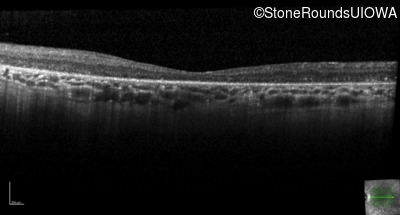

Optical Coherence Tomography - Right - 10/140 sc

Exemplar / OCT Stack